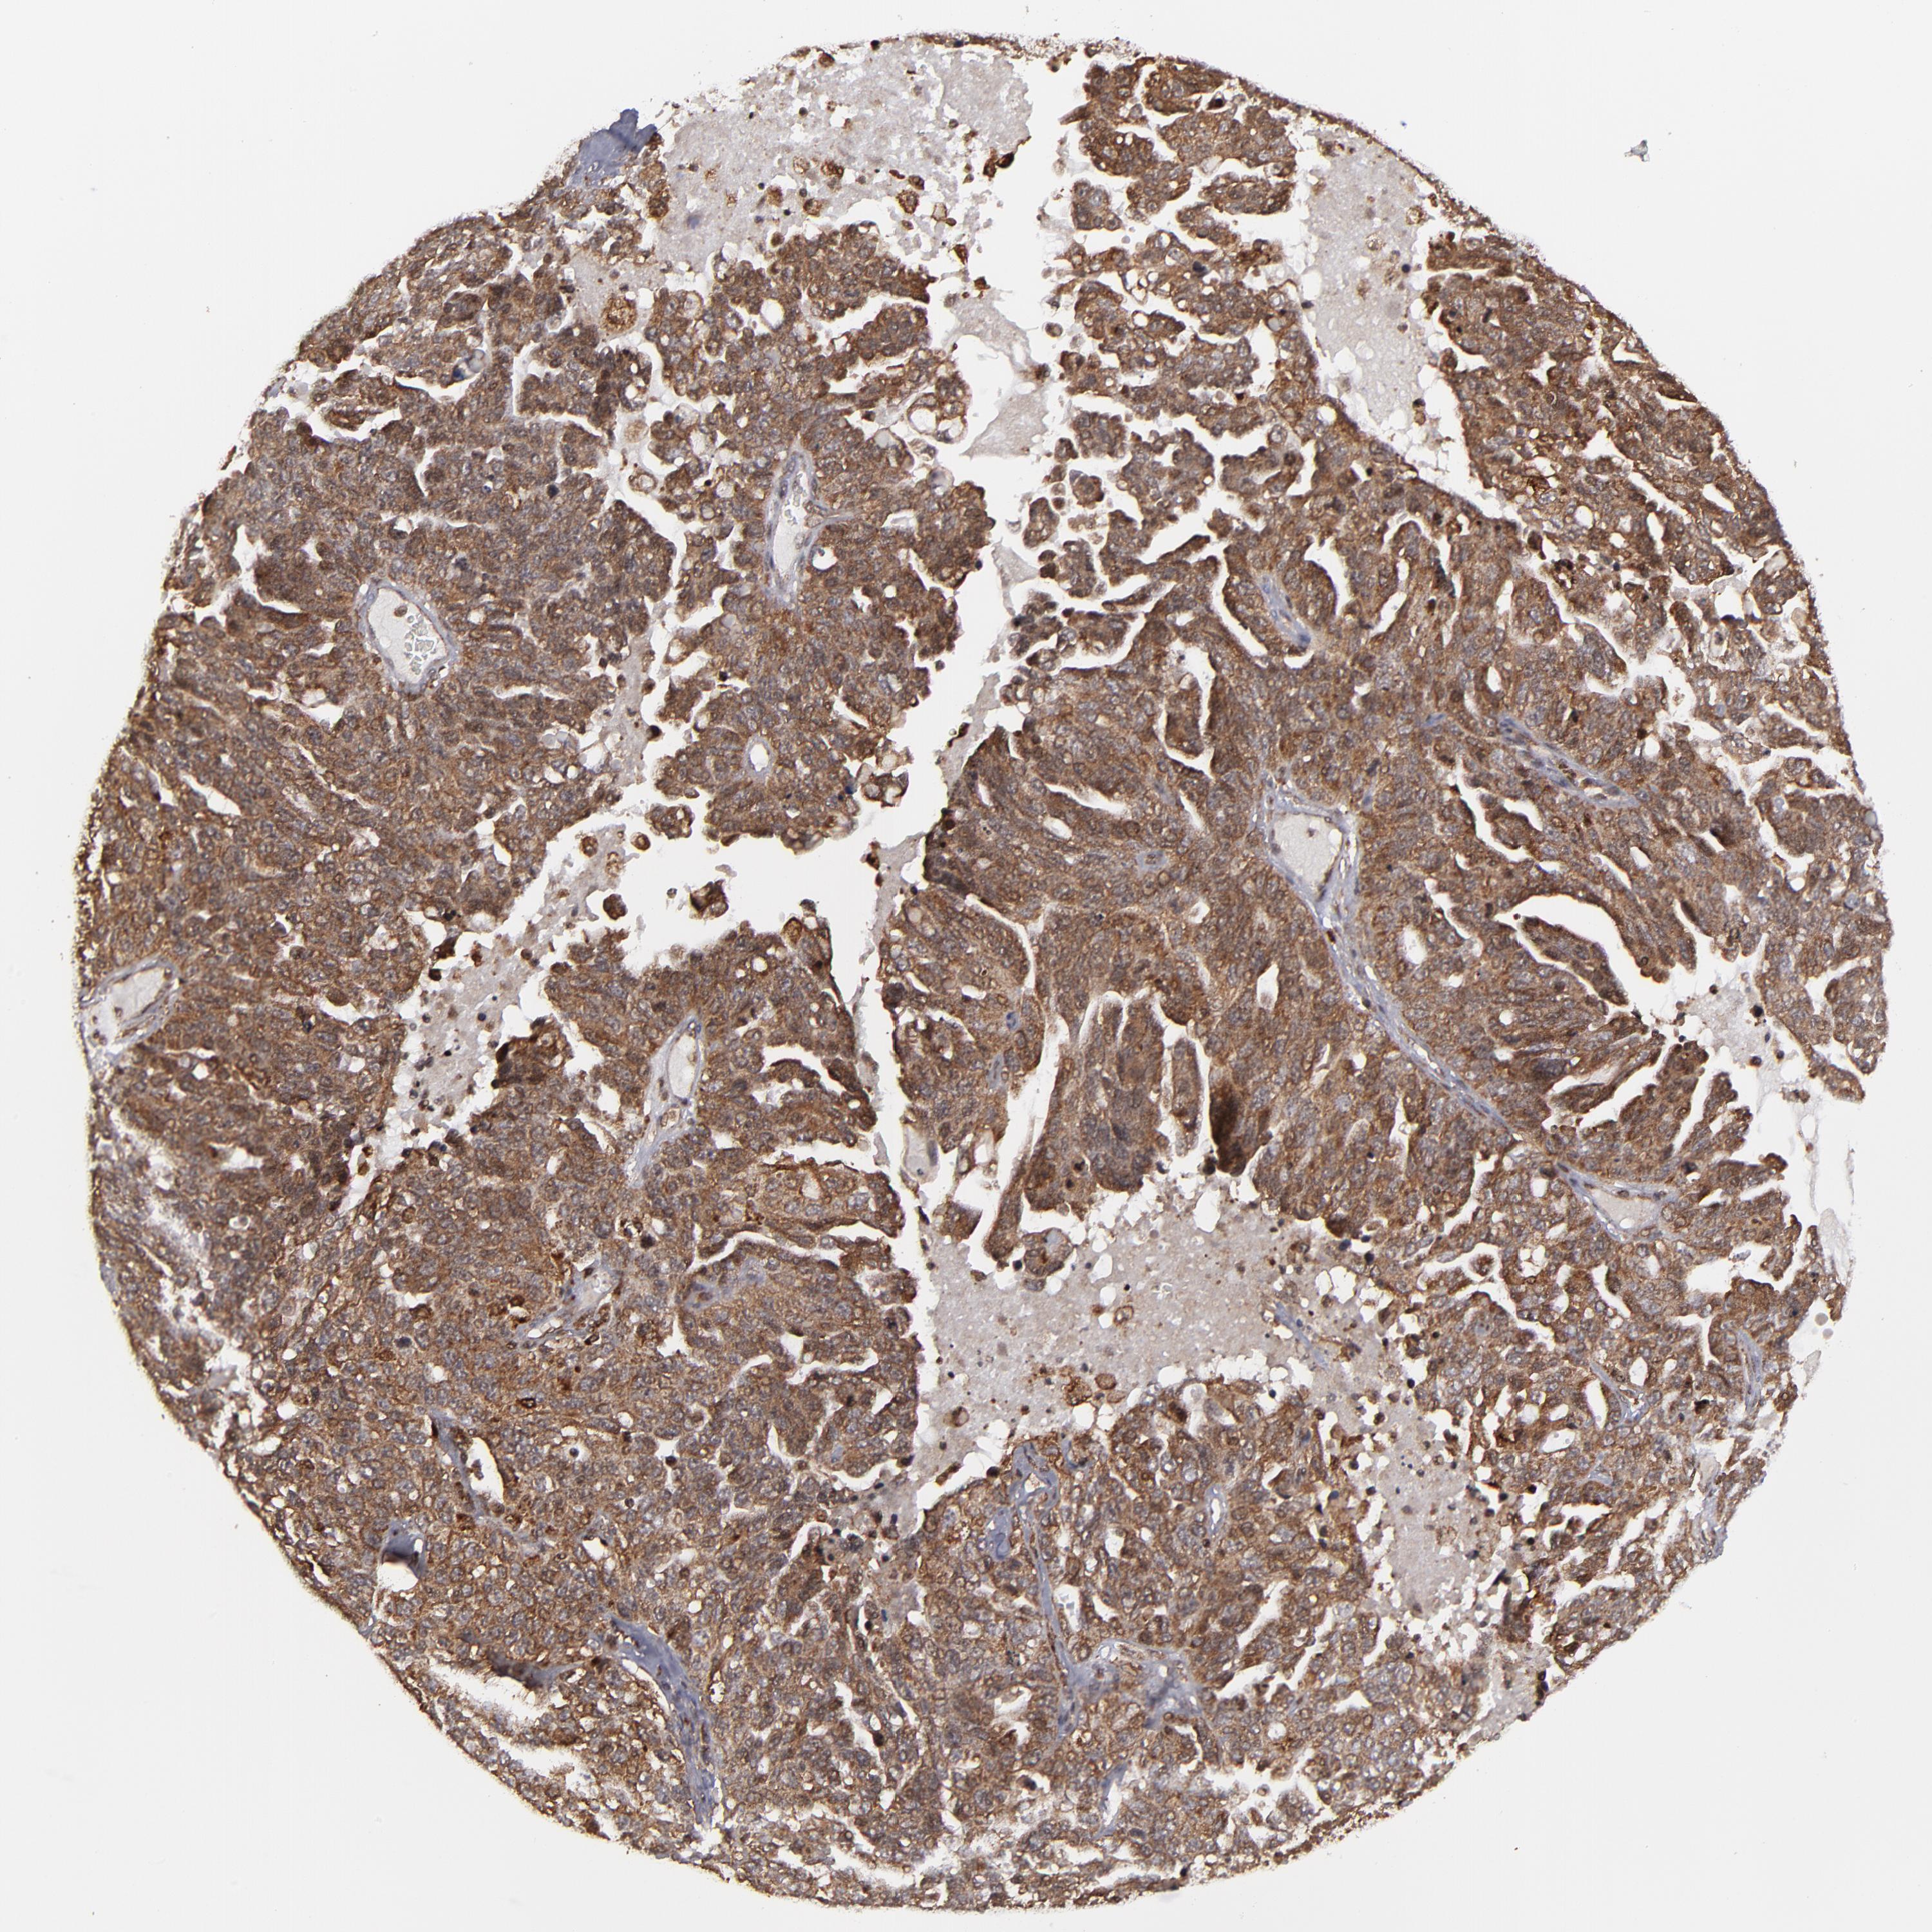

OVARIAN CANCER - Protein expressioni

A mouse-over function shows sample information and annotation data. Click on an image to view it in a full screen mode. Samples can be filtered based on level of antibody staining by selecting one or several of the following categories: high, medium, low and not detected. The assay and annotation is described here.

Note that samples used for immunohistochemistry by the Human Protein Atlas do not correspond to samples in the TCGA dataset.

Antibody stainingi

Antibody staining in the annotated cell types in the current human tissue is reported as not detected, low, medium, or high, based on conventional immunohistochemistry profiling in selected tissues. This score is based on the combination of the staining intensity and fraction of stained cells.

Each image is clickable and will lead to virtual microscopy that enables deeper exploration of all samples and also displays staining intensity scores, fraction scores and subcellular localization as well as patient and tissue information for each sample.

Antibody HPA003067

Staining

High

Medium

Low

Not detected

Intensity

Strong

Moderate

Weak

Negative

Quantity

>75%

75%-25%

<25%

None

Location

Nuclear

Cytoplasmic/membranous

Cytoplasmic/membranous,nuclear

Cystadenocarcinoma, serous, NOS

Cystadenocarcinoma, mucinous, NOS

Carcinoma, endometroid